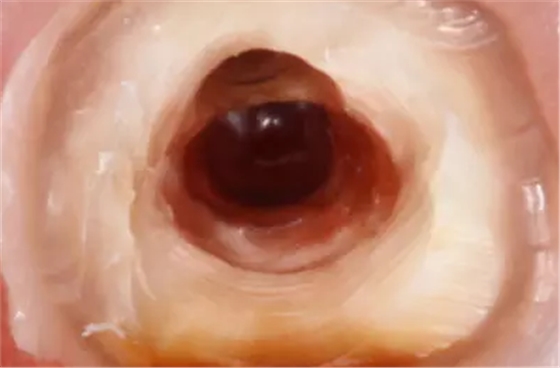

清理髓腔后,用中倍和高倍仔細(xì)查看穿孔的位置大小形狀和軟組織狀況。然后用小棉球?qū)⒏浇母芸诙氯?,以免異物掉入根管?nèi)。徹底清洗穿孔后,將調(diào)拌好的MTA材料充填到穿孔處,稍稍加壓,反復(fù)充填直到將穿孔填滿,使用小蒸餾水濕棉球整形,完成充填后,清理掉多余的材料,檢查外形。

因此,臨床上正確判斷穿孔的發(fā)生十分必要。穿孔出現(xiàn)的主要表現(xiàn)為:拔凈牙髓后,根管內(nèi)出血明顯,吸潮紙尖中部有血跡,尖端干凈;x線診斷絲從根管壁穿出;根管長(zhǎng)度測(cè)量?jī)x在根管銼未到工作長(zhǎng)度時(shí)顯示超出根尖孔;顯微鏡下能看到明顯的穿孔部位和牙周軟組織的粉紅顏色,或陳舊的壞死樣軟組織。